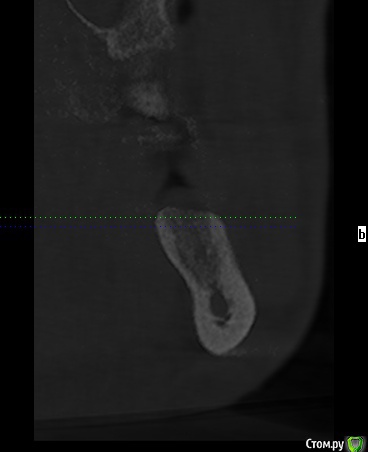

erm Опубликовано 2 февраля, 2016 Автор Поделиться Опубликовано 2 февраля, 2016 во еще снимок из клкт Ссылка на комментарий

erm Опубликовано 2 февраля, 2016 Автор Поделиться Опубликовано 2 февраля, 2016 попробуйте выложить срезы КТ той области, где удаляли зубвот не знаю оно или нет Ссылка на комментарий